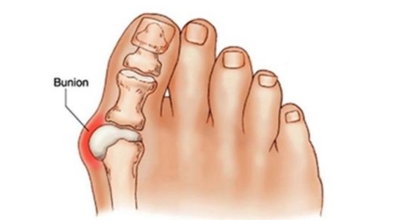

무지외반증 예방법

발볼이 좁은 신발이나 굽이 높은 신발을 신은 시간이 길수록 유병률이 더욱더 올라가기 때문에 발가락 부위가 넓고 굽이 낮은 신발을 착용하는 것이 좋으며, 평발인 경우 발바닥 안쪽을 지지해 주는 안창을 활용하는 것이 도움이 돼요. 다만 굽이 지나치게 낮은 신발은 쇼크을 완화해 주는 쿠션 역할이 이루어지지 않아서 피하며, 자신의 발에 맞는 편한 신발을 선택해서 피로도를 줄이는 것이 바람직합니다.